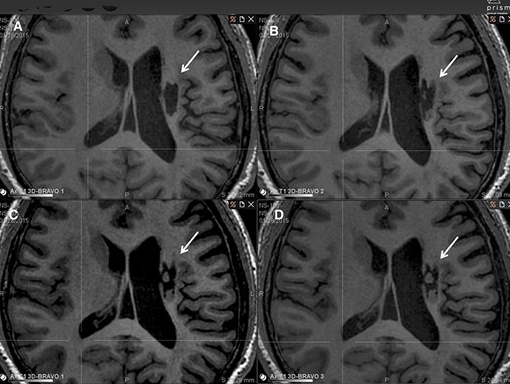

影像學(xué)檢查:在 6 個(gè)月的隨訪(fǎng)中,所有 9 名受試者均觀(guān)察到新組織,源自腦軟化梗塞腔。該腔內組織外觀(guān)具有以下特征:短期活力(術(shù)后第一次 MRI 與基線(xiàn)相比的組織外觀(guān))—9 例中有 9 例;生長(cháng)(術(shù)后至少兩次 MRI 中新組織增加)—6 例中有 6 例;穩定(術(shù)后至少兩次 MRI 中新組織沒(méi)有變化;即生長(cháng)平臺期,最長(cháng)為 24 個(gè)月)—6 例中有 5 例;無(wú)法獲得 24 個(gè)月后的長(cháng)期活力。

(A)基線(xiàn)時(shí),(B) 6 個(gè)月隨訪(fǎng)時(shí),(C) 12 個(gè)月隨訪(fǎng)時(shí),(D) 24 個(gè)月隨訪(fǎng)時(shí)。